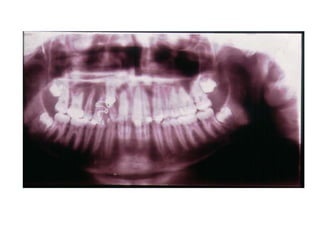

TRANSPOSIÇÃO TOTAL - CANINO COM INCISIVO LATERAL MANOBRAS PARA CORREÇÃO DA ROTA DE ERUPÇÃO